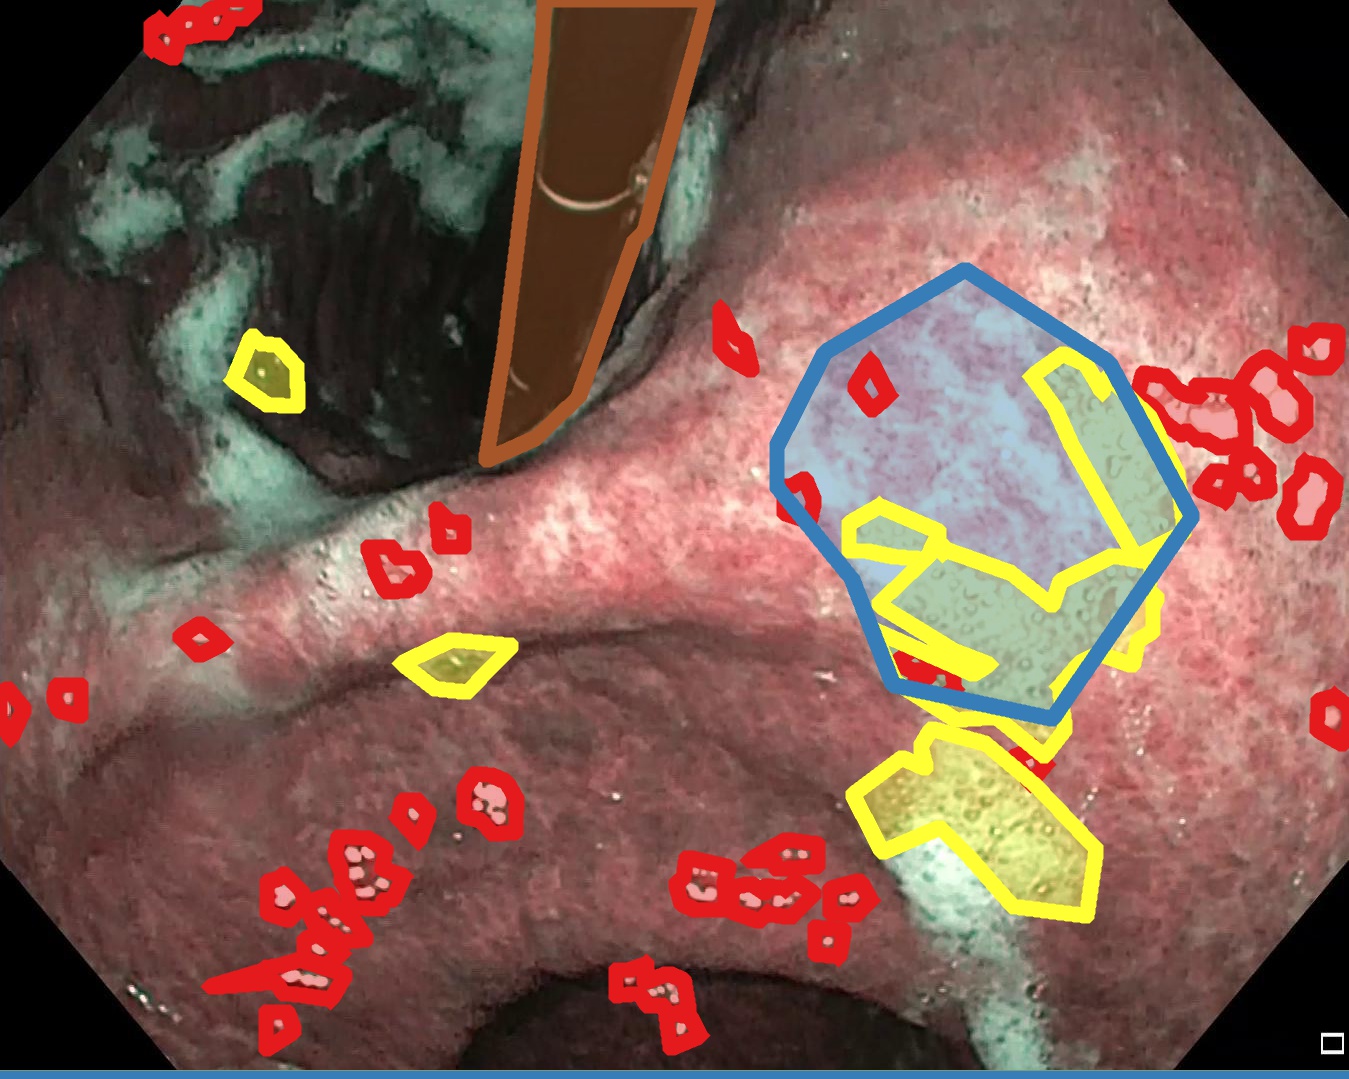

Examples for bounding box annotations for detection are shown in Fig. 2. It can be observed that while multiple boxes are annotated for several small specular areas; contrast, blur and instrument have relatively larger areas. Due to the overlap between two or more classes, the annotation by experts varied. This was minimized by following the detailed annotation protocol above. For semantic segmentation, a larger area mask was preferentially used to delineate locally very cluttered small specularity artifacts (see Fig. 3).